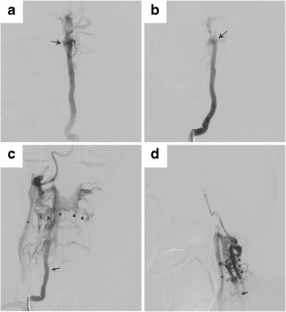

A previously healthy 53-year-old male presented with a 2-month history of pulsatile tinnitus, worsening headaches, and neck pain. Given the clinical symptoms, a workup was initiated to assess for a vascular etiology such as a dural arteriovenous fistula.

Choudhri, O., Dobre, M.C., Feroze, A. et al. Spontaneous regression of an idiopathic arteriovenous fistula of the right vertebral artery. Neuroradiology 60, 221–223 (2018). https://doi.org/10.1007/s00234-017-1963-3